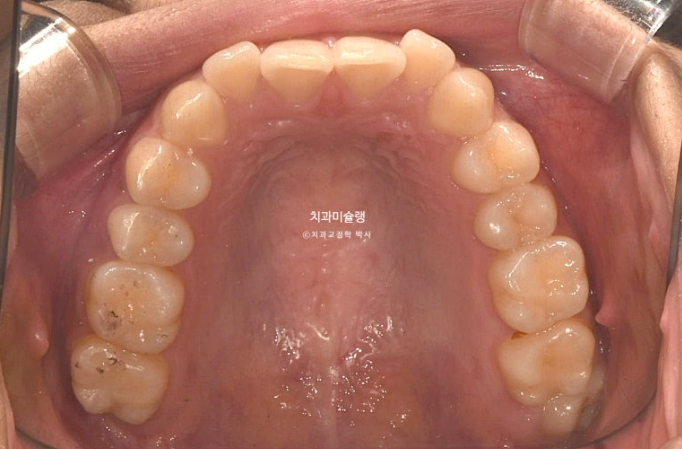

사랑니를 빼고 사랑니 공간으로 어금니를 후방이동 시켜 교합관계를 맞추고 덧니 해소할 공간을 얻기로 합니다.

돌출이나 뻗침은 없어서 비발치로 진행하는 것 입니다.

인비절라인 컴프레헨시브 프로그램으로 교정치료에 들어갔습니다.

첫세트 장치는 총 48개가 나왔습니다.

어금니 후방이동을 위해 교정용 나사 미니스크류가 안팎으로 심겨져있습니다.

어금니들은 사랑니 공간으로 후방이동 되었고 치근흡수는 없고 치근평행도는 좋습니다.